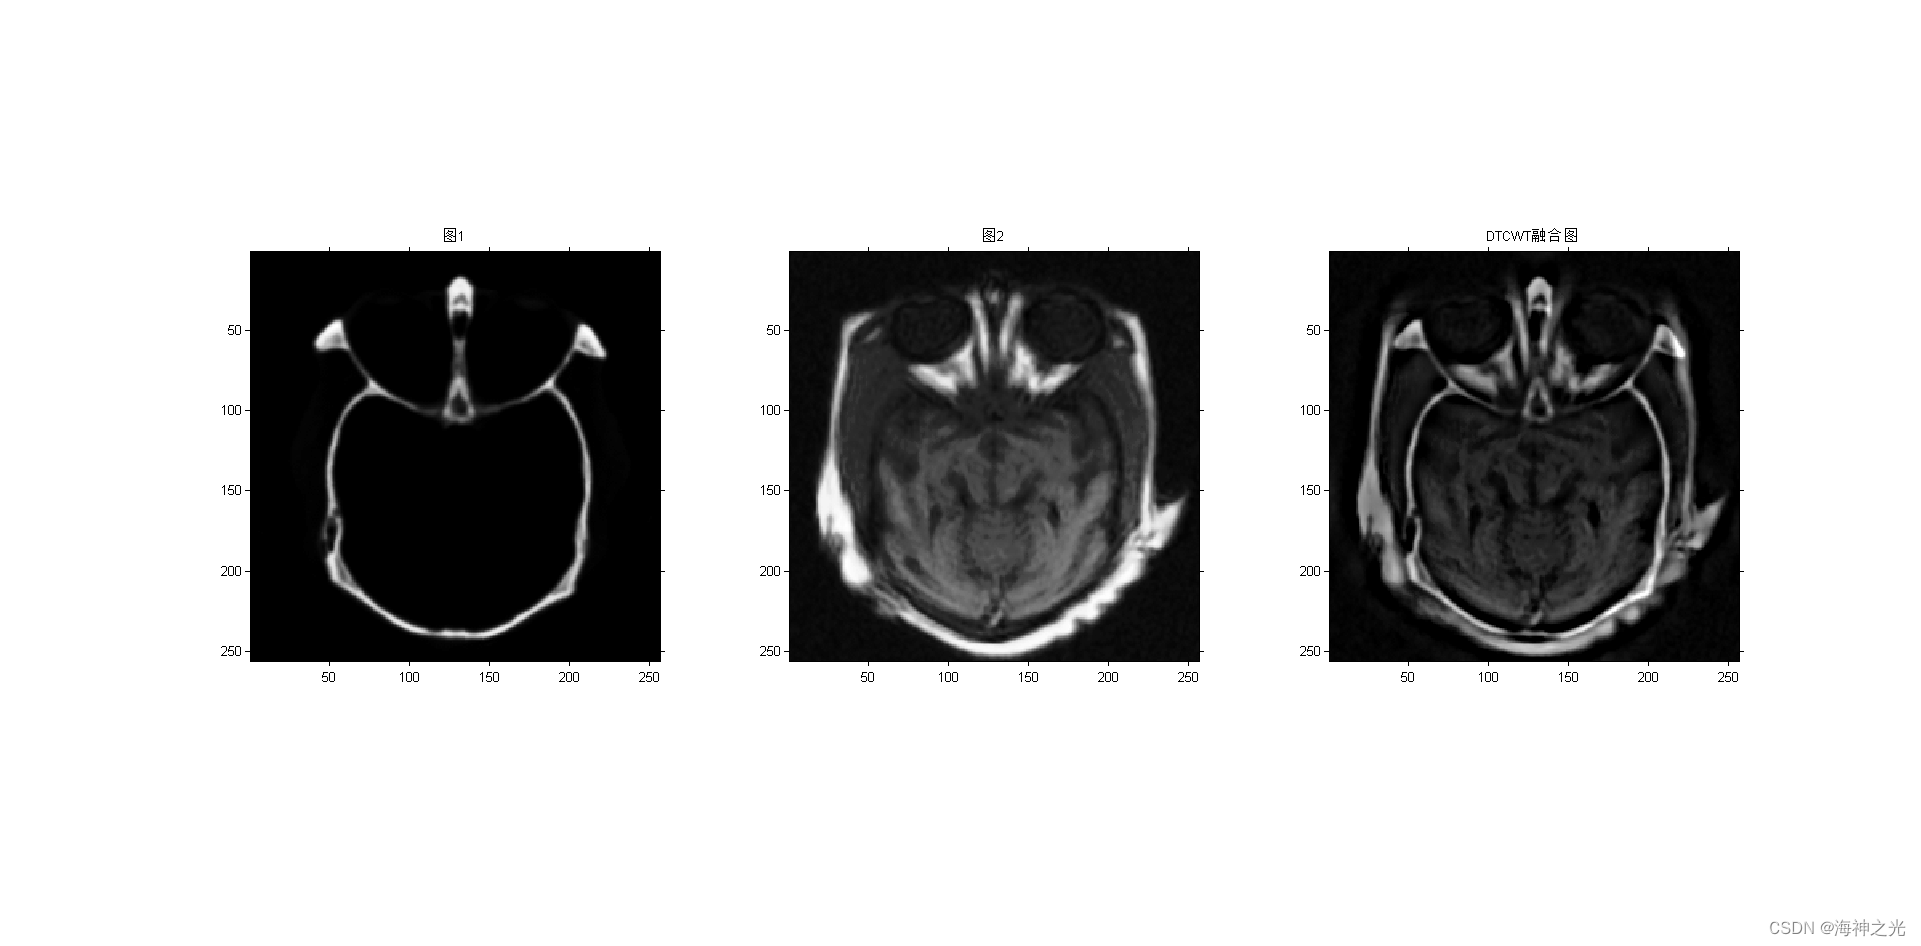

figure;subplot(131);imshow(image_input1);title(‘图1’)

subplot(132);imshow(image_input2);title(‘图2’)

subplot(133);

F = dtcwt_fuse(A,B,level); %DTCWT

title(‘DTCWT融合图’)

⛄三、运行结果